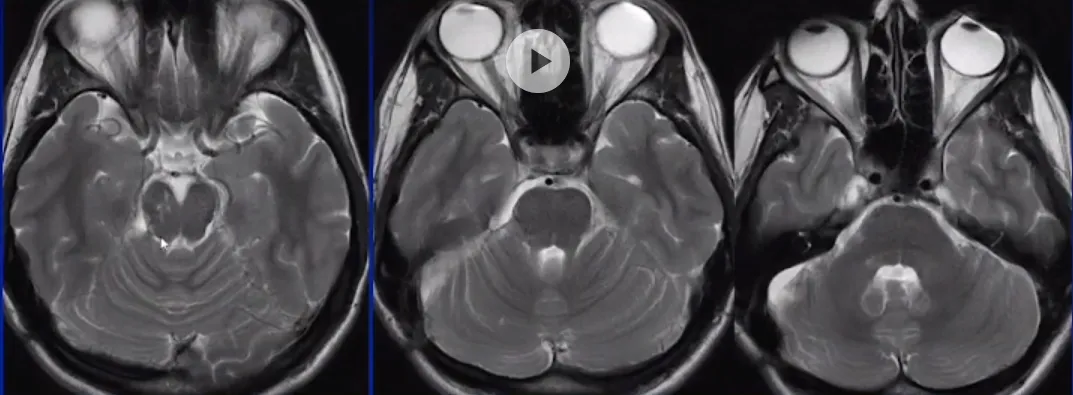

术后MRI

为了达到肿瘤的边边角角,术中需要采用30度、45度乃至70度内镜配合多角度专用器械实施切除。

该案例来自于施罗德教授《Endoscope-assisted mircosurgery in the Posterior fossa》演讲分享。